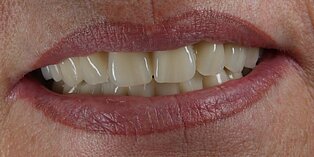

Vom Langzeitprovisorium zur TEK 1 Arbeit